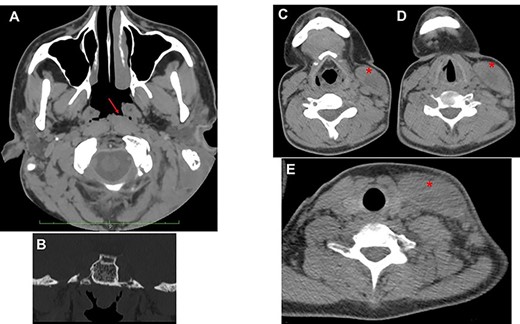

The otoscopic examination revealed bilateral perforation of the tympanic membrane and the presence of purulent discharge in the left ear (Fig. 1B). Nasal endoscopy identified II grade adenoid hypertrophy with complete obliteration of left choanal opening and tubal ostium (Fig. 2A and B). A pure tone audiometry, performed only through bone conduction, showed bilaterally normal auditory threshold. Neck ultrasound identified the presence of abundant fluid in the left latero-cervical area, which extended from the retro-auricular region up to the ipsilateral supraclavicular area.

(A) axial view; the red arrow shows edematous torus tubarius; compared to contralateral, the adenoid is hypertrophic but median; the presence of both these conditions contributes to ostium obstruction of the left tuba (B); (C–E) from top to down, the red asterisk shows the imbibition of sternocleidomastoid muscle sign of BA.

Head and neck contrast-enhanced computed tomography (CT) scan confirmed the presence of the fluid below the left sternocleidomastoid muscle (Fig. 2C–E) with massive opacification of the mastoid cells and the middle ear (Fig. 3A). Inflammatory tissue was identified in the middle ear with erosion of the ossicular bone chain (Fig. 3B). A diagnosis of CCOM with BA was made.